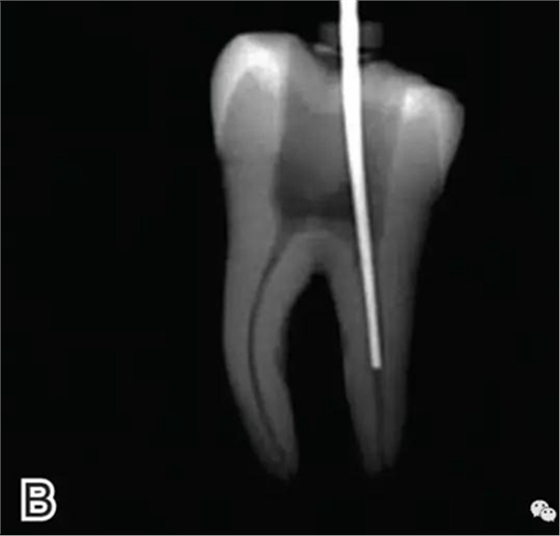

4、放置主尖及糊劑

將主尖的尖1/3 部分蘸一薄層根充糊劑,緩慢插入根管內(nèi),并左右旋轉(zhuǎn)主尖,以將根充糊劑均勻涂布于根管壁上,如圖4所示。

圖4 放置主尖及糊劑,A.放置主尖及糊劑 B.X線片下示主尖及糊劑的放置